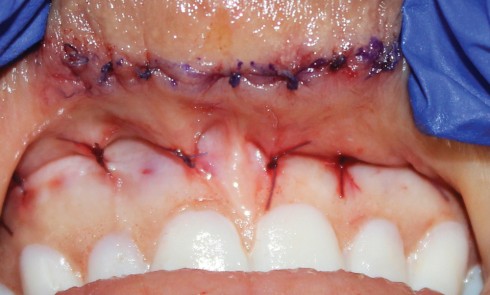

Article réservé à nos abonnés Corriger un sourire gingival grâce au repositionnement de la lèvre supérieure ou « lip repositioning »

L’exposition excessive de la gencive lors du sourire, connue sous le nom de sourire gingival, est une préoccupation esthétique pour...